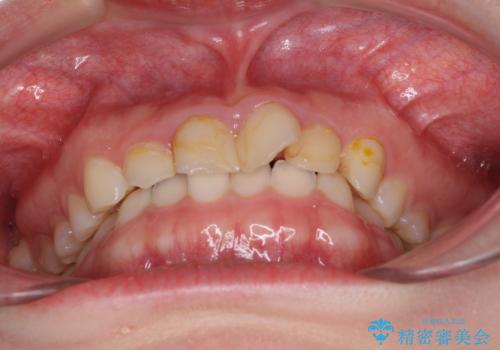

- 前歯の歯並びと虫歯を気にして来院された患者様です。

上下前歯の歯列不正はインビザラインにより歯列を整え、その後に、前歯5本をオールセラミッククラウンにて補綴治療することとしました。

矯正治療前に前歯のむし歯治療を行ったものの、樹脂で充填するには虫歯が広範囲であったため、審美的に問題がありました。